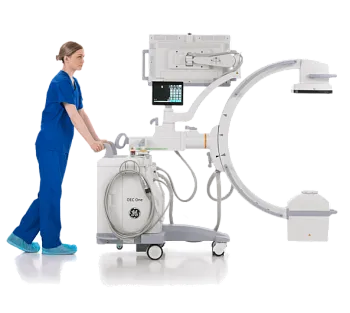

Компьютерный томограф GE HealthCare Revolution Aspire

Новинка от официального дистрибьютора МСТ.

Официальный дистрибьютор GE HealthСare с 2007 года